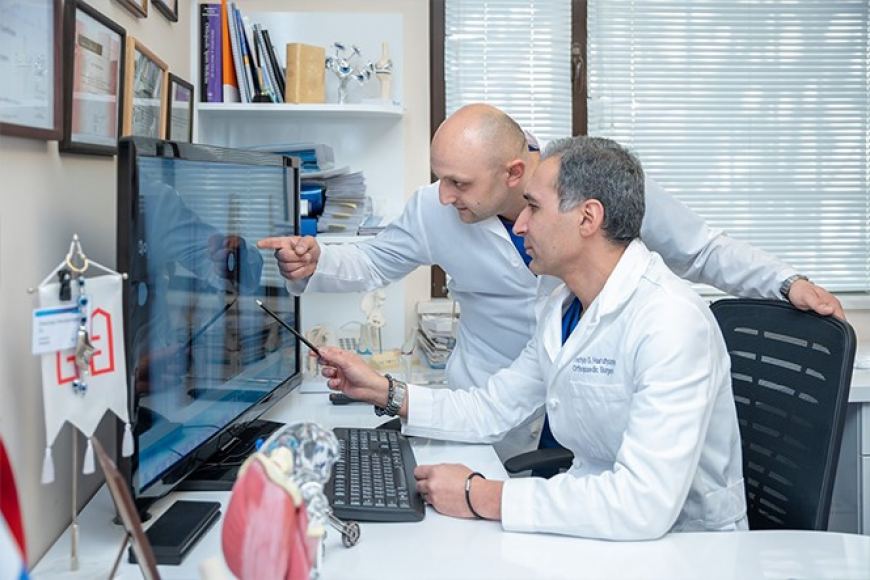

Orthopedics and Traumatology, "Coxa" Clinic

Orthopedics and Traumatology, "Coxa" Clinic

The orthopedic Traumatology Service performs the treatment of limbs and pelvic bones injuries, bone pathology, congenital and acquired malformations of the musculoskeletal system.

Modern methods of treatment and technologies proposed by the world's leading specialized associations (AO / ASIF, AAOS, etc.) are used.

The service performs organ-preserving surgeries. In case of spread bone diseases, bone and joint defects are removed, preserving a fully functional limb.